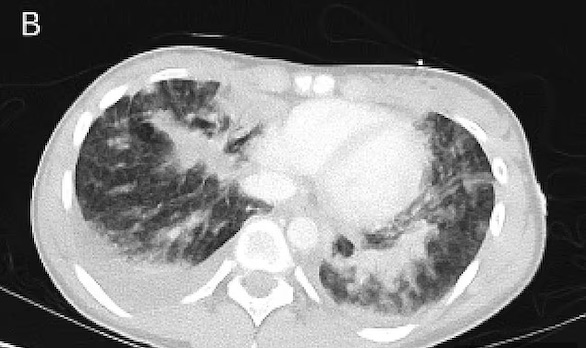

ويعتقد أطبائها في مستشفى راندويك للأطفال، أنها كانت تعاني من حالة رئوية تسمى "إيفالي" والتي ظهرت لأول مرة في الولايات المتحدة في عام 2019.

يُعتقد أن حالة "إيفالي" وهي اختصار باللغة الإنكليزية يشير إلى إصابات الرئة المرتبطة بالتدخين الإلكتروني، ناتجة عن تدخين سجائر إلكترونية تحتوي على رباعي هيدروكانابينول (THC)، وهي مادة ذات تأثير نفسي توجد أيضًا في الماريجوانا، ومضافات فيتامين E أسيتات.

وبعد أن خرجت داكوتا من المستشفى بعد أسبوع من تلقي العلاج، كانت هناك أورام غير طبيعية تسمى العقيدات لا تزال تظهر في فحوصات الرئة، مما شكل تهديداً خطيراً على حياتها.